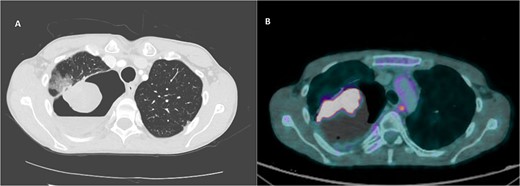

A 36-year-old male was referred to the Thoracic Surgery Service due to an incidental finding of a 5-cm soft tissue density within a known long-standing large right apical bulla on a chest X-ray (Fig. 1A). This lesion was new compared to the patient’s last chest X-ray 5 months prior (Fig. 1B). A computed tomography (CT) scan of the chest, abdomen, and pelvis demonstrated a 4.4 × 5.2 cm intracavitary solid-appearing mass within the wall of the longstanding bulla, along with heterogeneous fluid layering within the cavity with questionable enhancement (Fig. 2). This was reported as concerning for a primary bronchogenic malignancy (versus adherent fungus ball) with a superimposed infection. The patient had no respiratory or constitutional symptoms.

CT imaging of right intracavitary lung mass found within the wall of a longstanding bulla, along with heterogeneous fluid layering within the cavity (A). The mass was reported to be 4.4 × 5.2 cm and was concerning for primary bronchogenic malignancy. This lesion increased to 6.8 × 5.9 cm, demonstrating intense increased FDG activity and interval increase in fluid layering within the bulla within 2 months on follow-up PET imaging (B).

A PET scan done 2 months after the original CT scan showed that the lesion had increased in size (3.3 × 6.8 × 5.9 cm compared to previous CT findings of 2.7 × 3.9 cm), and demonstrated intense increased fludeoxyglucose (FDG) activity, with several smaller foci of similar intense grade FDG avid soft tissue nodules along the posterior aspect of the inferior bulla (Fig. 2). There was also an interval increase in fluid layering within the bulla. There was no distant metastasis.